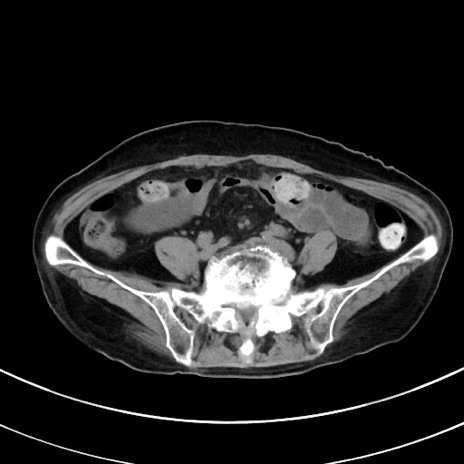

症例33(横断像)

【症例】70歳代 女性

【主訴】心窩部痛

【現病歴】延髄病変の精査・加療にて神経内科入院中。本日より心窩部痛あり。

【既往歴】虫垂炎

【身体所見】右下腹部を中心に圧痛と反跳痛あり。

【データ】WBC 10900、CRP 0.02